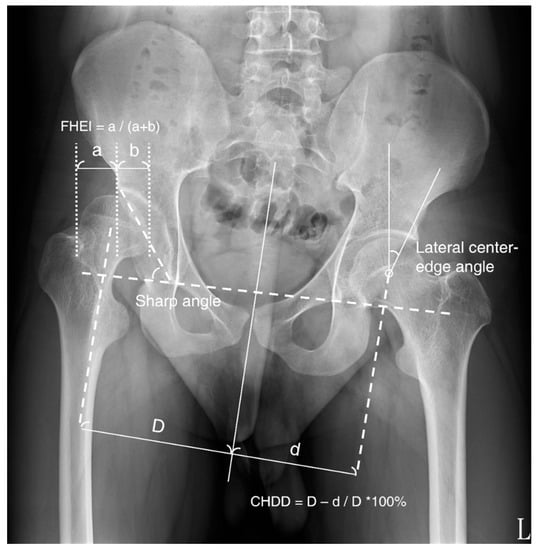

We reviewed the retrospective clinical charts and preoperative and postoperative radiographs of all patients. AP standing radiographs were used to assess the extent of hip dysplasia, and radiographic parameters for acetabular morphology were collected for comparison, specifically Sharp’s angle (SA), the lateral centre-edge angle (CE angle), the femoral-head extrusion index (FHEI), and the centre-head distance discrepancy (CHDD; Figure 1). The CE angle is formed between a line drawn from the centre of the femoral head to the lateral edge of the acetabulum and a second line that is parallel to the longitudinal pelvic axis [10,11]. SA, also known as acetabular angle, is measured by a horizontal line drawn between the bilateral teardrops (inferior end projection of the acetabular fossa floor) and an additional line extending to the lateral acetabular roof [12]. FHEI is the percentage of the femoral head not covered by the acetabulum. The centre-head distance is the distance from the centreline of the body to the femoral head, and CHDD is defined as the difference in centre-head distance between the affected and normal sides [13].

Figure 1.

Radiographic outcome parameters on AP standing radiographs of the pelvis. FHEI: femoral-head extrusion index, CHDD: centre-head distance discrepancy.